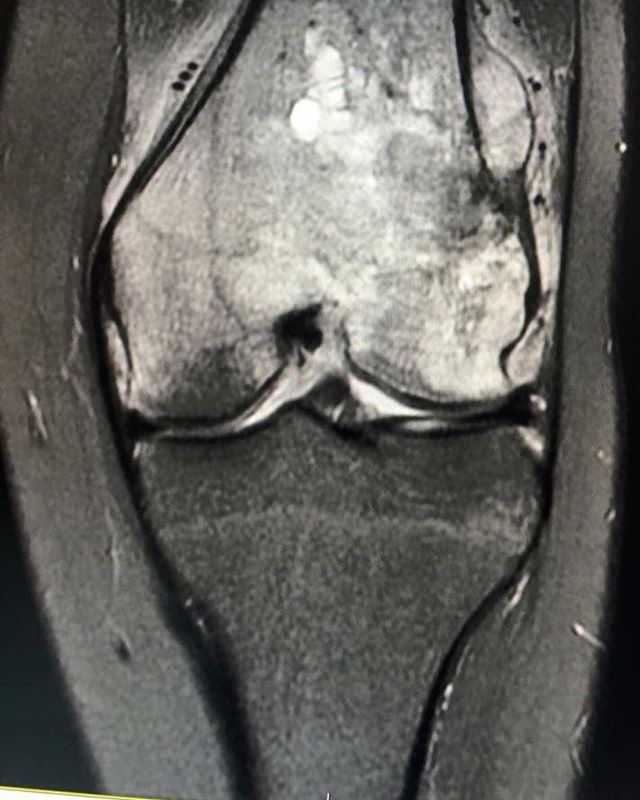

I was diagnosed with osteosarcoma in my femur on 29th of February 2016. I was 16 years old...